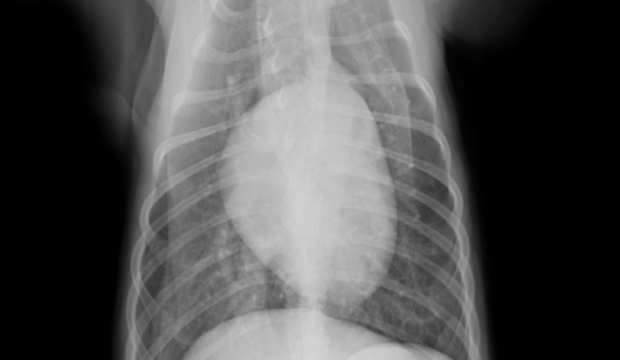

全身麻酔下で歯のレントゲンを撮影すると歯の付け根あたりから歯が溶けたように吸収されて一部骨に置き換わっているのが分かります。